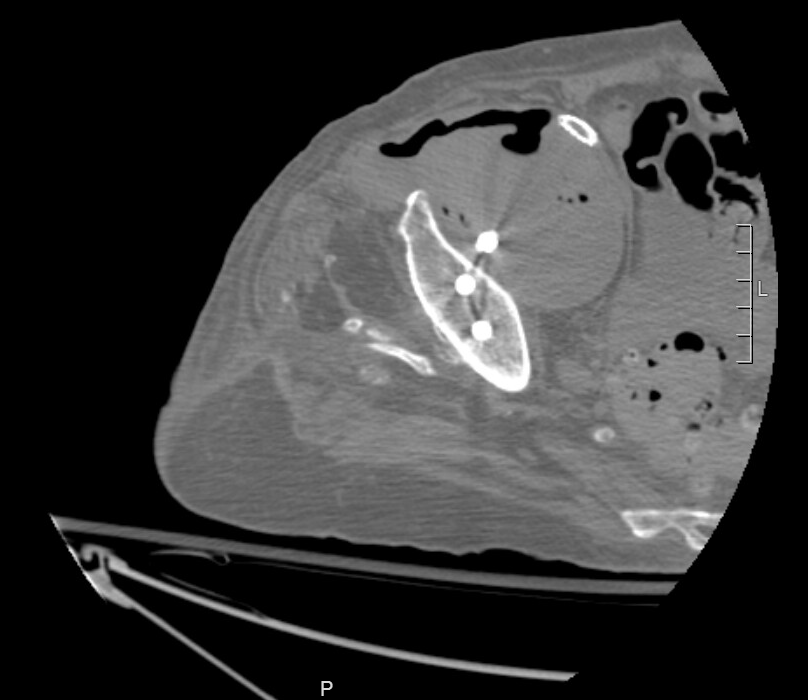

A month earlier, she’d been found to have a large pseudoaneurysm arising from her external iliac artery. (And yes, that’s a screw from a previous hip replacement traversing it.) She underwent stenting and returned home.

Because she was septic and in pain, we scanned her again. The new CT showed extensive gas within the pseudoaneurysm. It was now infected, and that was a big problem.